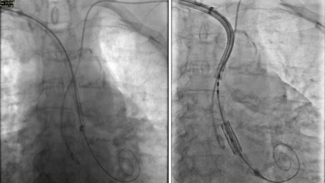

Traditionally, percutaneous mitral commissurotomy (PMC) is performed under fluoroscopy only. In difficult cases, general anesthesia with transesophageal echocardiography (TEE) guidance is needed. Intracardiac echocardiography (ICE) enables...